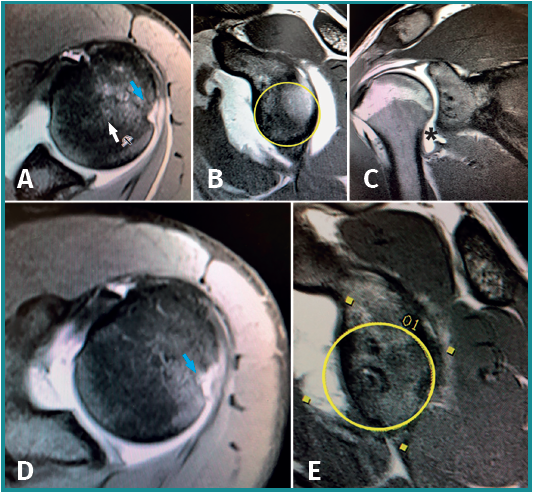

A comparative analysis was made of the dimensions of the shoulder bone defects before and after primary surgery failure. An increase in lesion size was recorded for both the humeral head and the glenoid cavity following failure of the previous operation (Figure 1).

The mean HSI prior to surgery was 1.4 cm (range 0.8-1.8). The mean HSI after surgical failure was 1.8 cm (range 0.9-2.6 ); the difference proved statistically significant (p = 0.004). The mean depth of the Hill-Sachs lesion was 0.4 cm (range 0.2-0.8) before the operation, versus 0.5 cm (range 0.25-0.8) after relapse. The differences were not significant (p=0.1).

The bony Bankart lesion showed the greatest increase in size between primary surgery, with a mean preoperative defect of 9.6% (range 0-29%), and surgical failure, with a mean defect of 18.7% (range 8-36%). The differences were statistically significant (p=0.006). Only two of the 9 patients had a preoperative glenoid defect of over 15%, while after surgical failure 6 patients had bone defects of over 15% and two subjects presented substance losses in excess of 25% (Figure 2).

Before primary Bankart surgery, only one of the 9 shoulders presented an off-track lesion according to the head-glenoid cavity index. However, following the failure of Bankart repair, 7 of the 9 lesions were considered to be off-track.